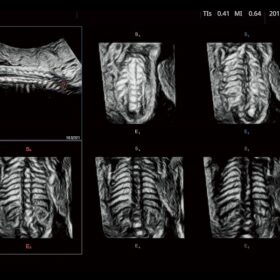

FUTUS features great imaging technologies to support a clear view and confident diagnoses.